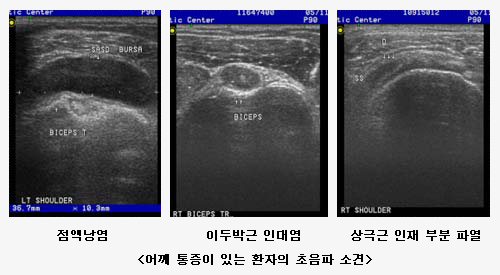

°üÀý ÃÊÀ½ÆÄ Ŭ¸®´Ð |

Ãâó : ·ù¸¶Æ¼½º³»°ú - È«½ÂÀç ±³¼ö ÃÖÁ¾¼öÁ¤ : 2004.11.15 ÀÔ·Â: 2004.11.15 |

°æÈñÀÇ·á¿ø ·ù¸¶Æ¼½º ³»°ú¿¡¼´Â ±Ù°ñ°Ý°è ÃÊÀ½ÆÄ¸¦ ÀÌ¿ëÇÏ¿© ·ù¸¶Æ¼½º °üÀý¿°, ÅðÇ༺ °üÀý¿°, Åëdz¼º °üÀý¿°, °Á÷¼º ôÃß¿°µîÀÇ ´Ù¾çÇÑ °üÀýÁúȯÀ» Áø´ÜÇϰí Ä¡·áÇϴµ¥ ÀÌ¿ëÇÏ¿© È¿°úÀûÀÎ Áø·á¿¡ ¸¹Àº µµ¿òÀÌ µÇ°í ÀÖ½À´Ï´Ù. ¶ÇÇÑ, ·çÇÁ½º, º£Ã¼Æ®¿Í °°Àº ÀÚ°¡¸é¿ªÁúȯ¿¡¼ µ¿¹ÝµÉ ¼ö ÀÖ´Â ±Ù°ñ°Ý°è ÁúȯÀ» Áø·áÇϴµ¥µµ ÃÊÀ½ÆÄ °Ë»ç¸¦ ÅëÇØ Áø·áÀÇ ÁúÀ» ³ôÀ̰í ÀÖ½À´Ï´Ù. °üÀý¾×À» ¹è¾×ÇÏ¿© °Ë»çÇϰí Ä¡·áÀû ¸ñÀûÀ¸·Î °üÀý¾× õÀÚ¸¦ ½ÃÇàÇϱ⵵Çϸç, µ¿½Ã¿¡ °üÀý°³» Áֻ縦 ½ÃÇàÇÒ ¼ö ÀÖ½À´Ï´Ù. ÀÌ·¯ÇÑ ¼ö±â¸¦ ½ÃÇàÇÒ¶§ º¸´Ù Á¤È®ÇÑ Á¢±ÙÀ» À§ÇØ ÃÊÀ½ÆÄ·Î Á÷Á¢ È®ÀÎÇÏ¸é¼ ½ÃÇàÇÏ°Ô µÇ¾î ½Ã¼ú ºÎÀÛ¿ëÀ» ÃÖ¼ÒÈ ÇÒ ¼ö ÀÖ½À´Ï´Ù.